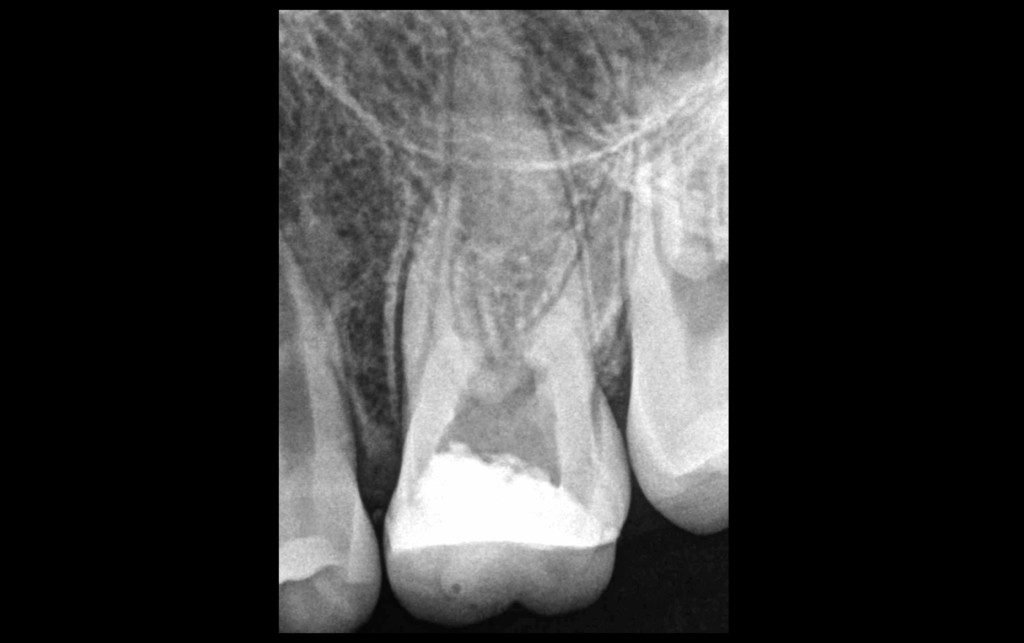

🦷 𝐓𝐫𝐚𝐢𝐭𝐞𝐦𝐞𝐧𝐭 𝐩𝐫𝐞́𝐜𝐞́𝐝𝐞𝐦𝐦𝐞𝐧𝐭 𝐢𝐧𝐢𝐭𝐢𝐞́,

𝐎𝐬 𝐩𝐞́𝐫𝐢 𝐚𝐩𝐢𝐜𝐚𝐥 𝐧𝐨𝐫𝐦𝐚𝐥

❗ Pourtant l’allodynie mécanique est bien là (douleur à la percussion).

🤔 𝐏𝐨𝐮𝐫𝐪𝐮𝐨𝐢 ?

🔎 Indices :

📍 Épaississement ligamentaire

📍 Sondage vestibulaire à 6 – 8 mm